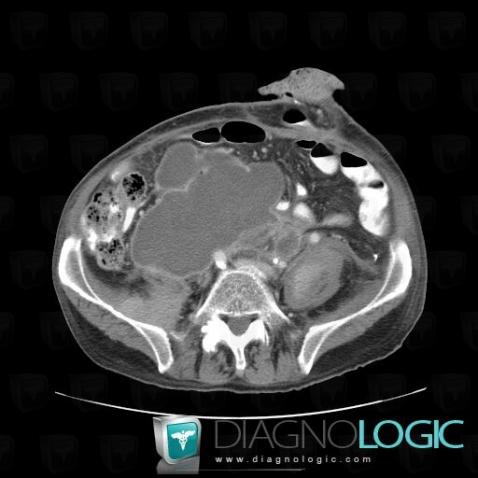

Abscess, Retroperitoneum, CT

Here is the specific information in the key image above:

- Diagnosis Abscess, Location(s) Retroperitoneum, with gamuts Low density retroperitoneal mass, Cystic retroperitoneal mass